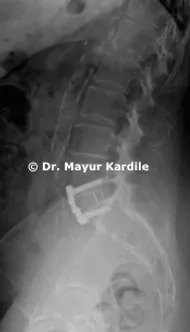

Anterior Lumbar Interbody Fusion (ALIF) for L5-S1 Recurrent Disc Herniation with Foraminal Stenosis

A 67-year-old lady suffered from severe left side leg pain. She had an L5-S1 discectomy 8 years back and was doing perfectly well after that. She started having leg pain for the past 6 months

MRI revealed recurrent disc herniation at L5-S1 with foraminal stenosis on left side

Anterior Lumbar Interbody Fusion (ALIF) surgery was done on her and she had a dramatic relief from leg pain.

ALIF provides indirect decompression of the spinal nerves and is an excellent technique to avoid nerve roots that are already scarred in case of revision spine surgery.

Also, it restores the normal lordotic angle of the lumbar motion segment